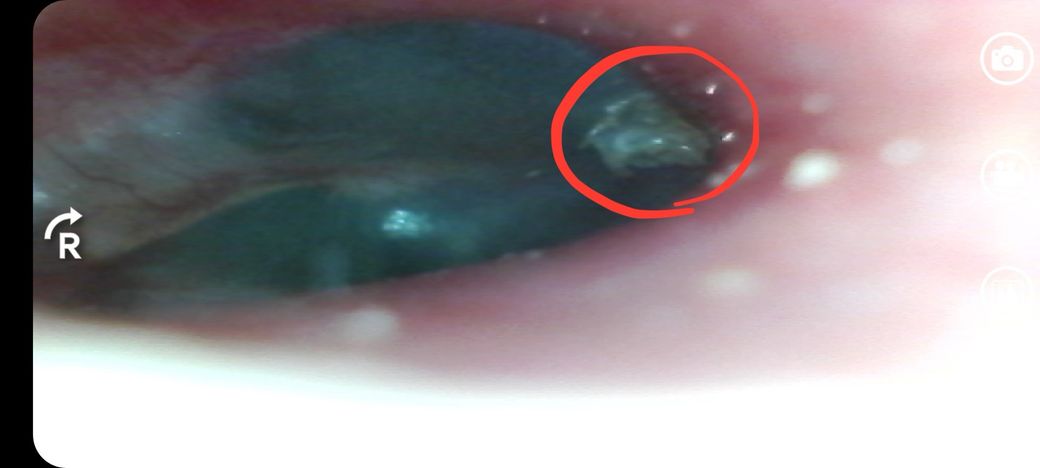

왼쪽 귀가 먹먹해요 고막사진좀 봐주세요

샤워하고나서 왼쪽 귀가 먹먹해서 귀 고막 사진 찍었는게 저렇게 뭔가 기포처럼 있네요 저거 뭔가요 괜찮은건가요

오른쪽은 고막 깨끗해요

• 1번 째 사진